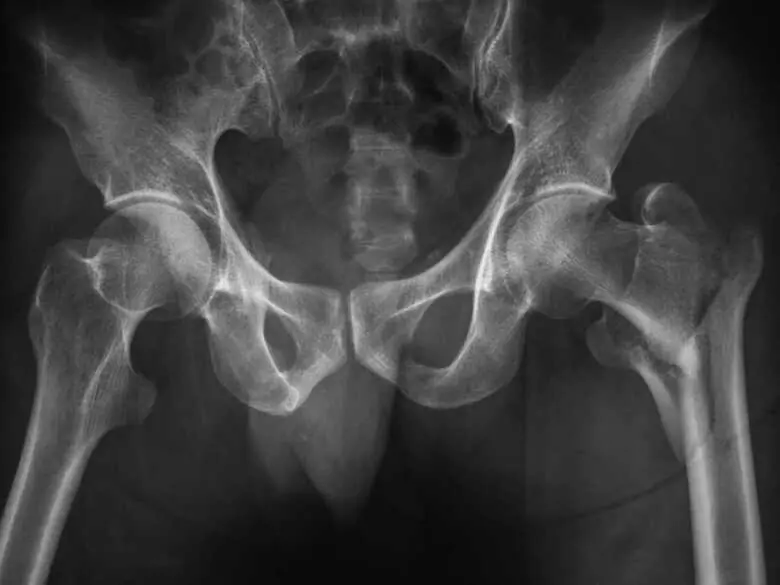

Foto de rayos X caderas